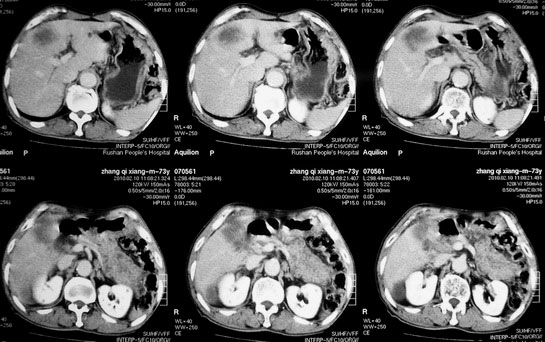

肝胆管细胞癌

患者AFP正常,无肝病病史。CA199 1000ng/ml,CEA偏高。血象WBC正常,N偏高。

化脓性胆囊炎累及肝脏;胆管细胞癌;肝转移瘤

活检病理

:是

胆管细胞癌

这个病人开始就是主要鉴别的肝脓肿和胆管细胞癌。可是增强后环征也不明显,占位内造影也非常不明显。这种情况怎么判断?谢谢大家。

病灶强化幅度较轻,低密度坏死区内见无定形高密度影,是其特点。